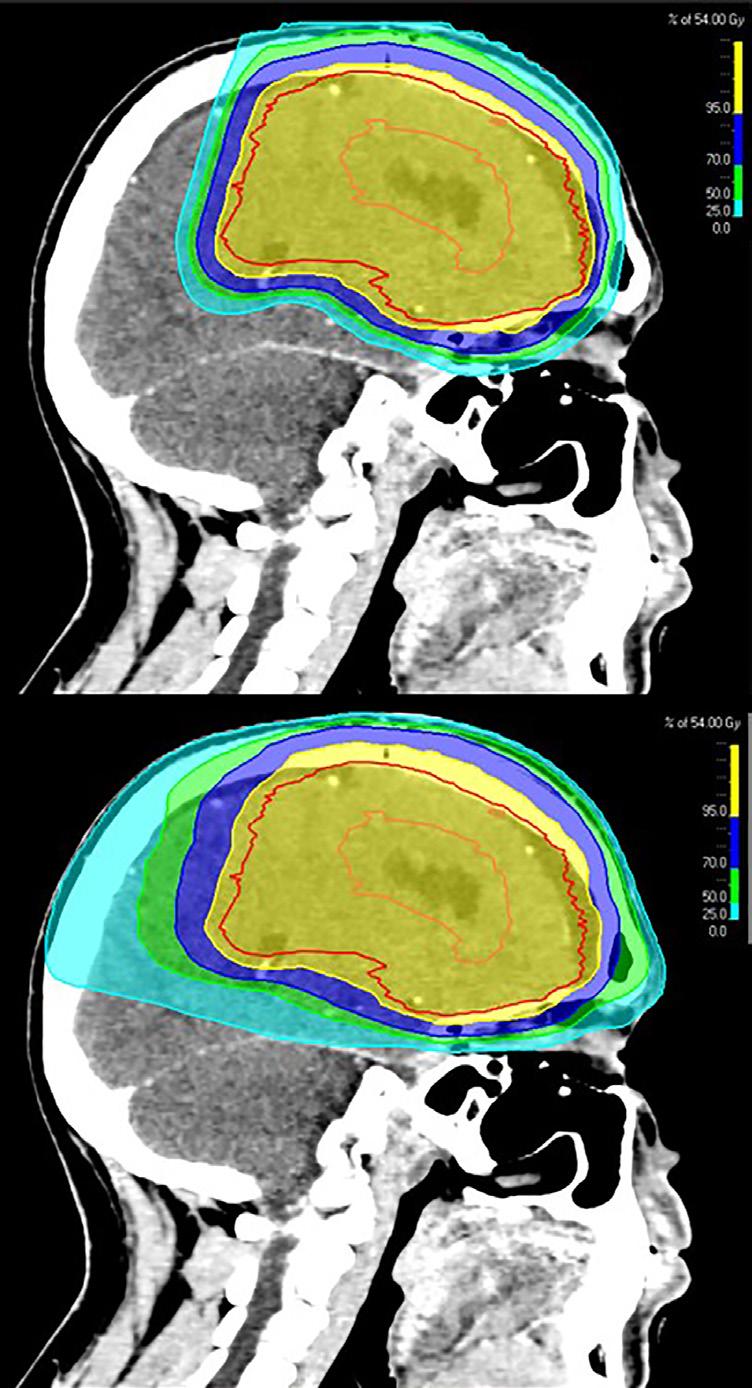

Året 2024 er i gang, og det er mye å se frem til i år. Til sommeren blir for eksempel EM i fotball i Tyskland (... nå glemte jeg et øyeblikk at mesterskapet går uten Norge ��) og når vi kommer til desember skal de første pasientene få proton-strålebehandling i Norge. Dette blir en spennende prosess å følge. Ikke minst blir det spennende å følge med på hvordan lik tilgang til behandlingen sikres for pasienter fra hele landet og hvordan man skal få gitt en stor del av behandlingene som ledd i kliniske studier.